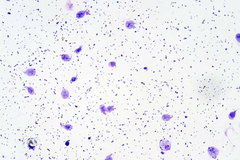

Nổi phân ly tâm bằng kẽm sulfat (trọng lượng riêng là 1,18) (SOP 2) là xét nghiệm được lựa chọn để nhìn thấy nang Giardia trong phân. Nang có hình bầu dục, dài 10-12 μm và có thành mỏng bao quanh. Ở con vật bị tiêu chảy, phết phân mới có thể giúp hiển thị các dưỡng thể di chuyển, có chuyển động ‘lá rơi’ điển hình.